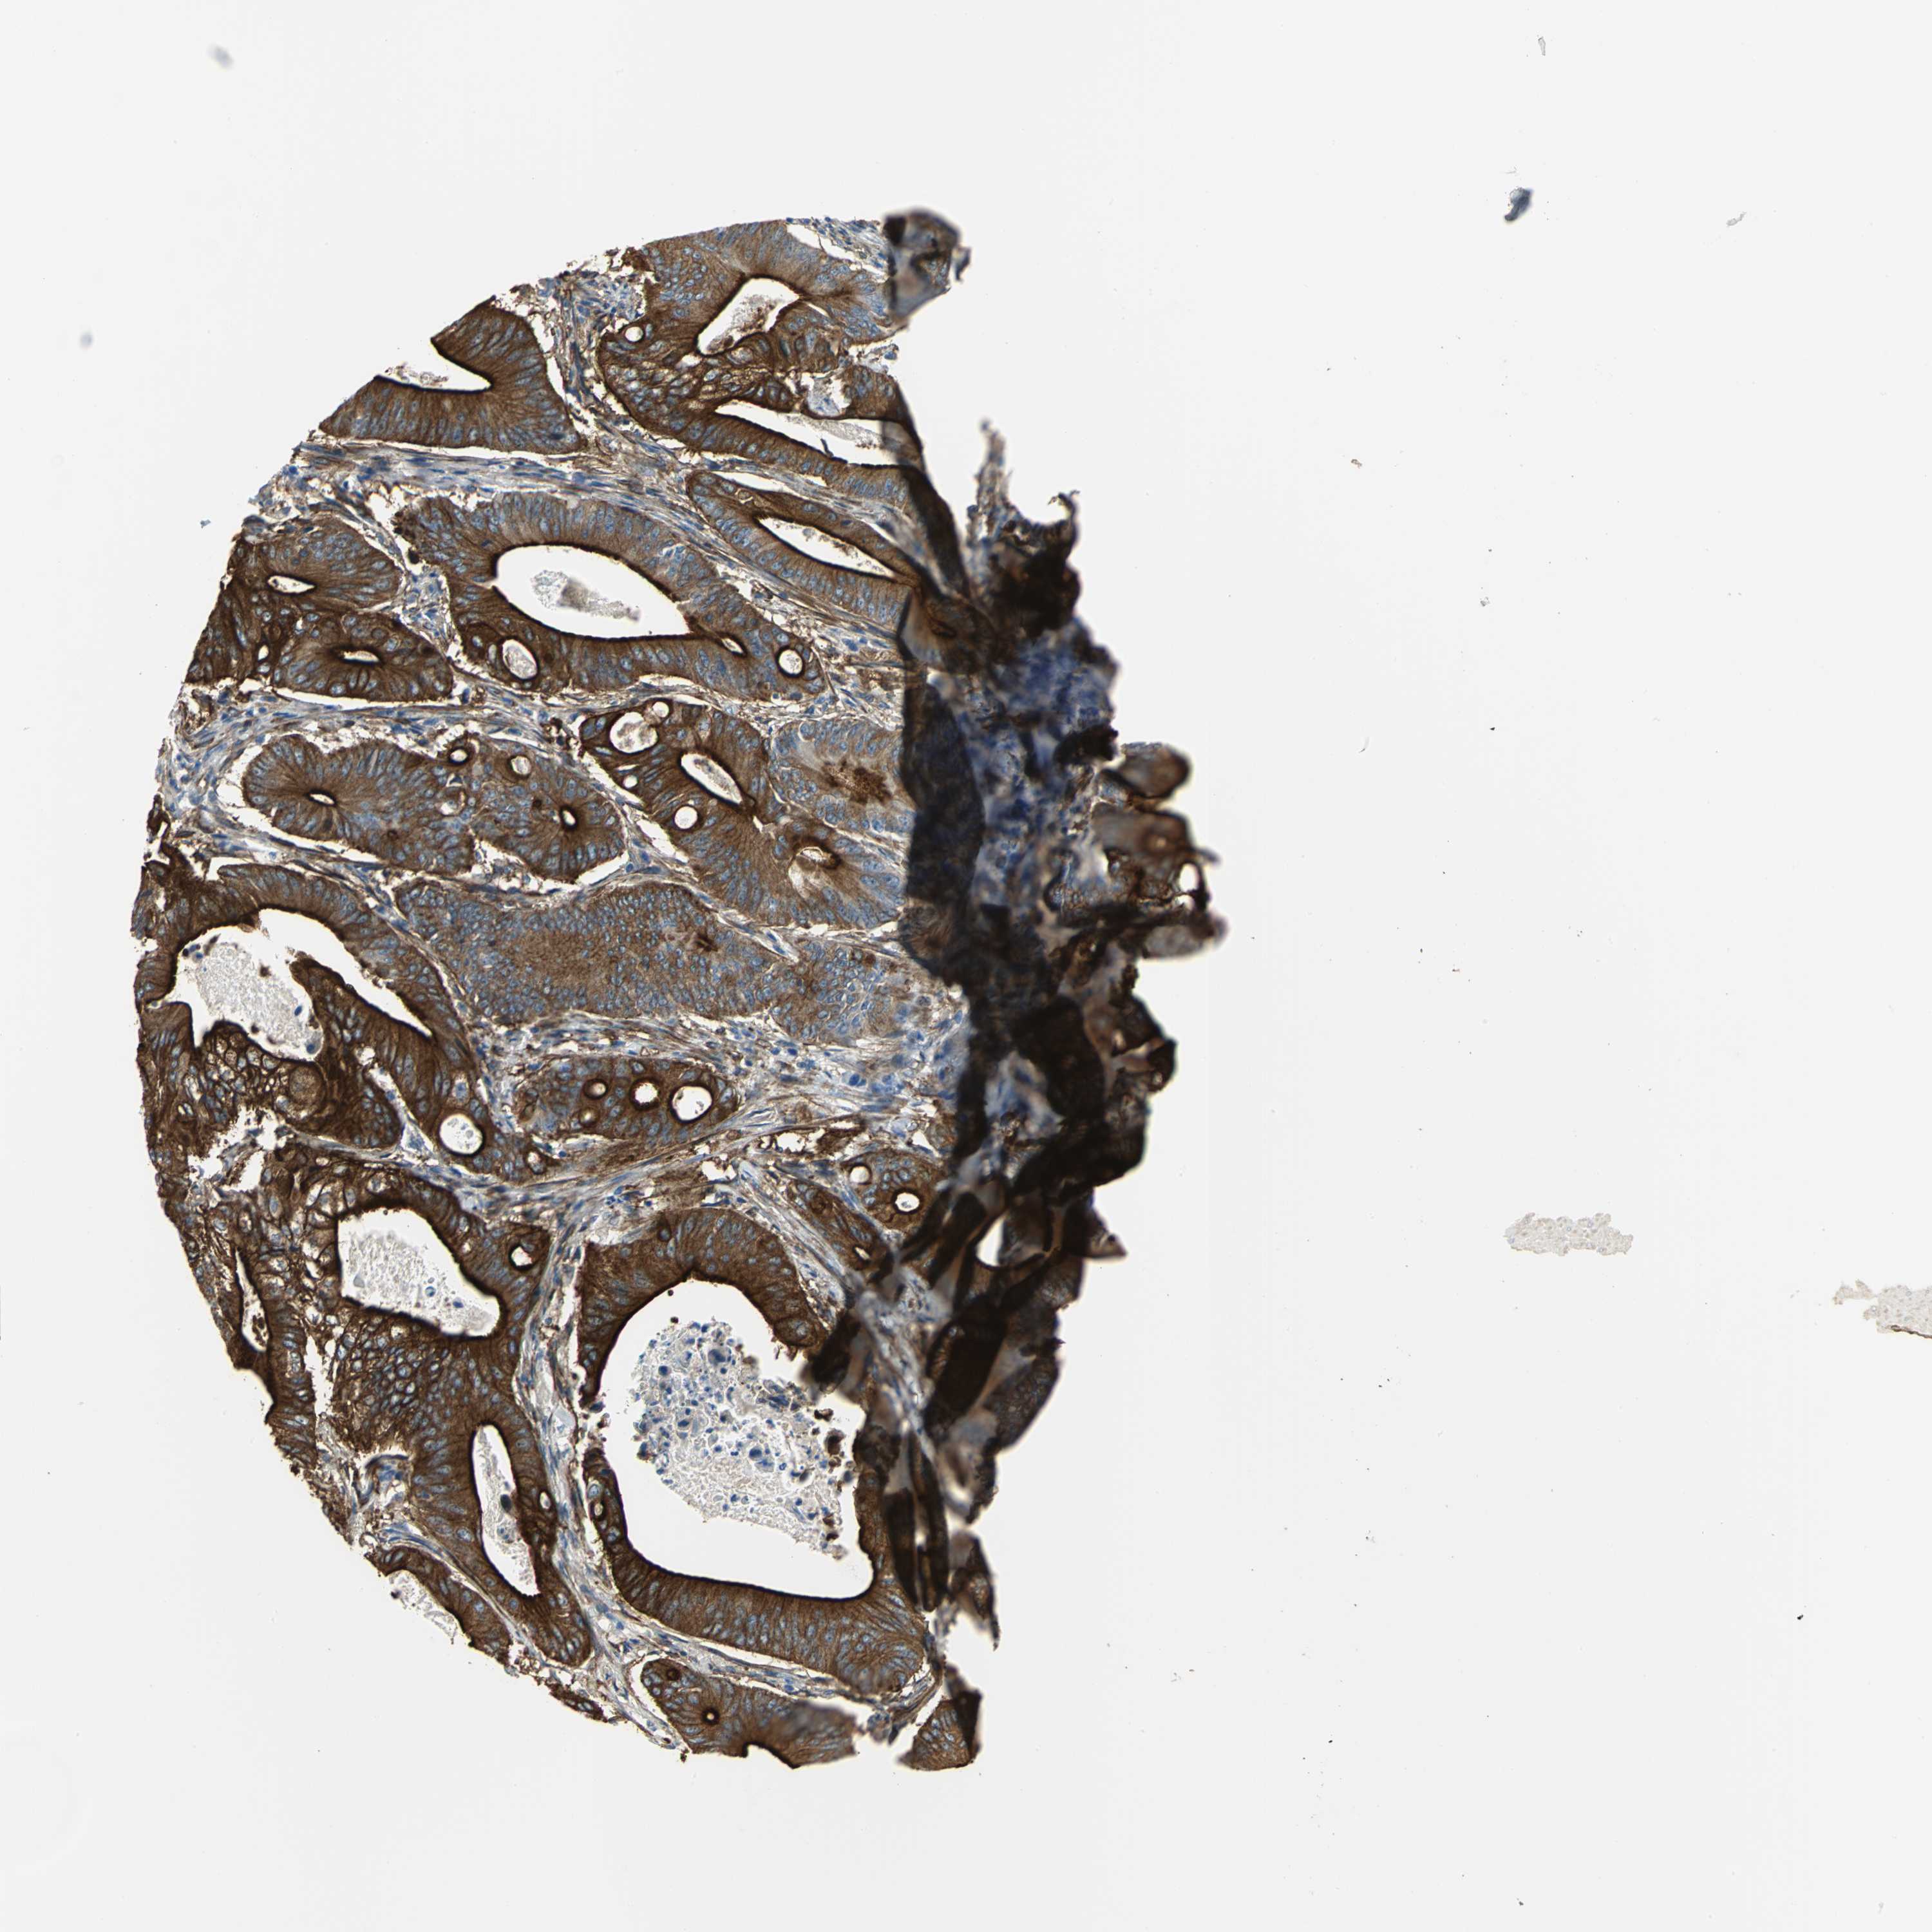

PANCREATIC CANCER - Protein expressioni

A mouse-over function shows sample information and annotation data. Click on an image to view it in a full screen mode. Samples can be filtered based on level of antibody staining by selecting one or several of the following categories: high, medium, low and not detected. The assay and annotation is described here.

Note that samples used for immunohistochemistry by the Human Protein Atlas do not correspond to samples in the TCGA dataset.

Antibody stainingi

Antibody staining in the annotated cell types in the current human tissue is reported as not detected, low, medium, or high, based on conventional immunohistochemistry profiling in selected tissues. This score is based on the combination of the staining intensity and fraction of stained cells.

Each image is clickable and will lead to virtual microscopy that enables deeper exploration of all samples and also displays staining intensity scores, fraction scores and subcellular localization as well as patient and tissue information for each sample.

Antibody HPA004747

Antibody HPA004886

Antibody CAB019322

Adenocarcinoma, NOS

Adenocarcinoma, metastatic, NOS